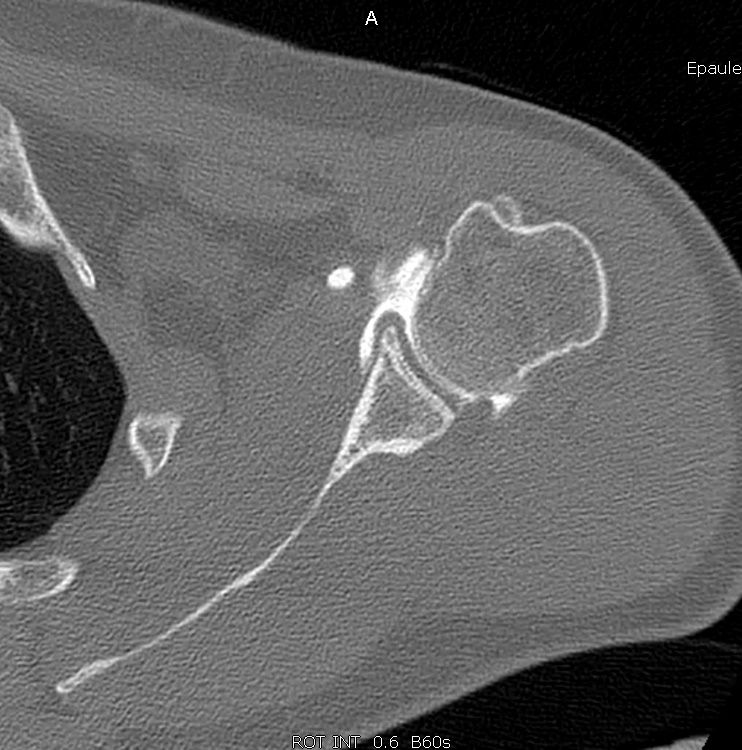

A CT scan is the best way to both analyse bone lesions and search for glenoid hypoplasia, dysplasia or retroversion as predisposing factors (Fig 1). Posterior labral damage on contrast-enhanced images may also indicate a labral fissure (Fig. 2). However, any such capsulolabral detachment is only pathological if located at the inferior, subequatorial portion of the bone.

Likewise, take time to check for any associated cartilage damage since this is a very important prognostic factor, as discussed below. For detecting soft tissue lesions and cartilage defects MR imaging is superior to CT and can also be done as Arthro-MRI.